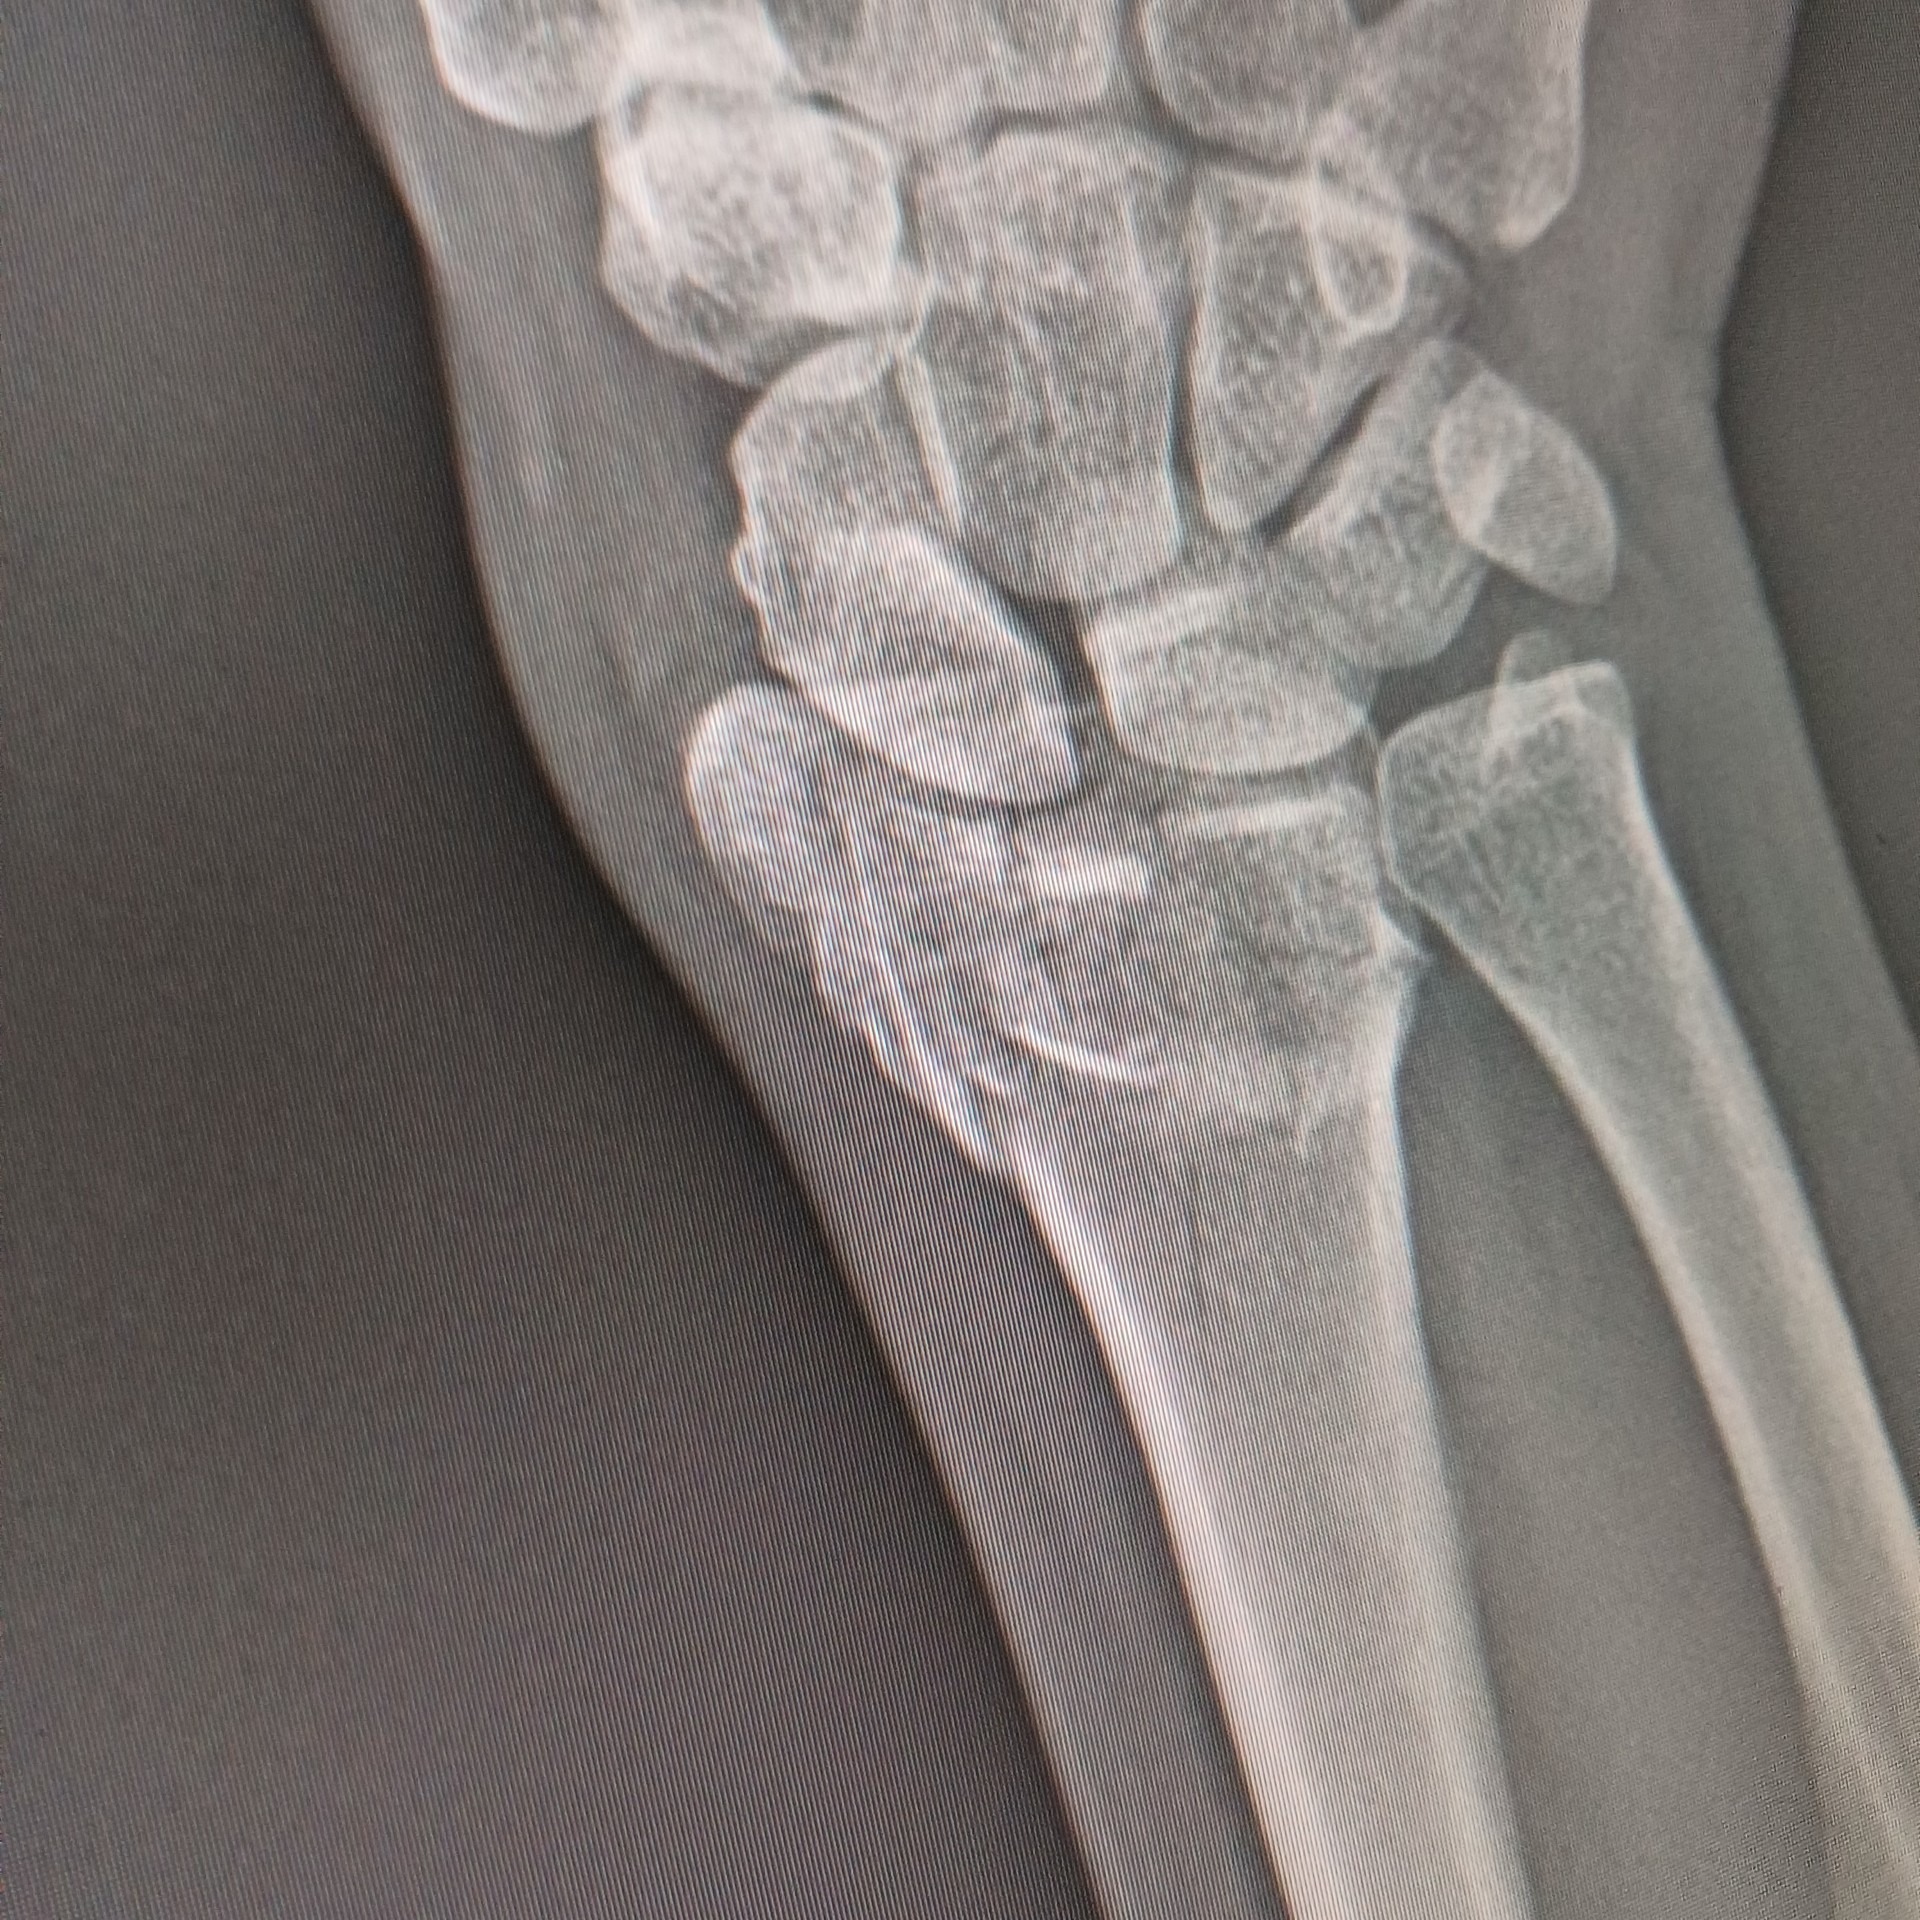

I have a Distal Radius Fracture... and it got fractured in many pieces and the pieces displaced. I'm currently dealing with pain but managing.

After consulting with the specialist, its been determined i will need surgery, which involves getting the wrist open and a metal plaque installed